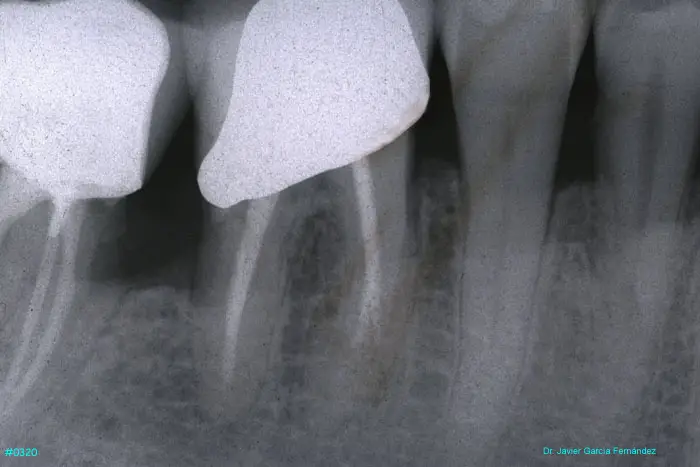

ATLAS DE CIRUGIA PERIODONTAL